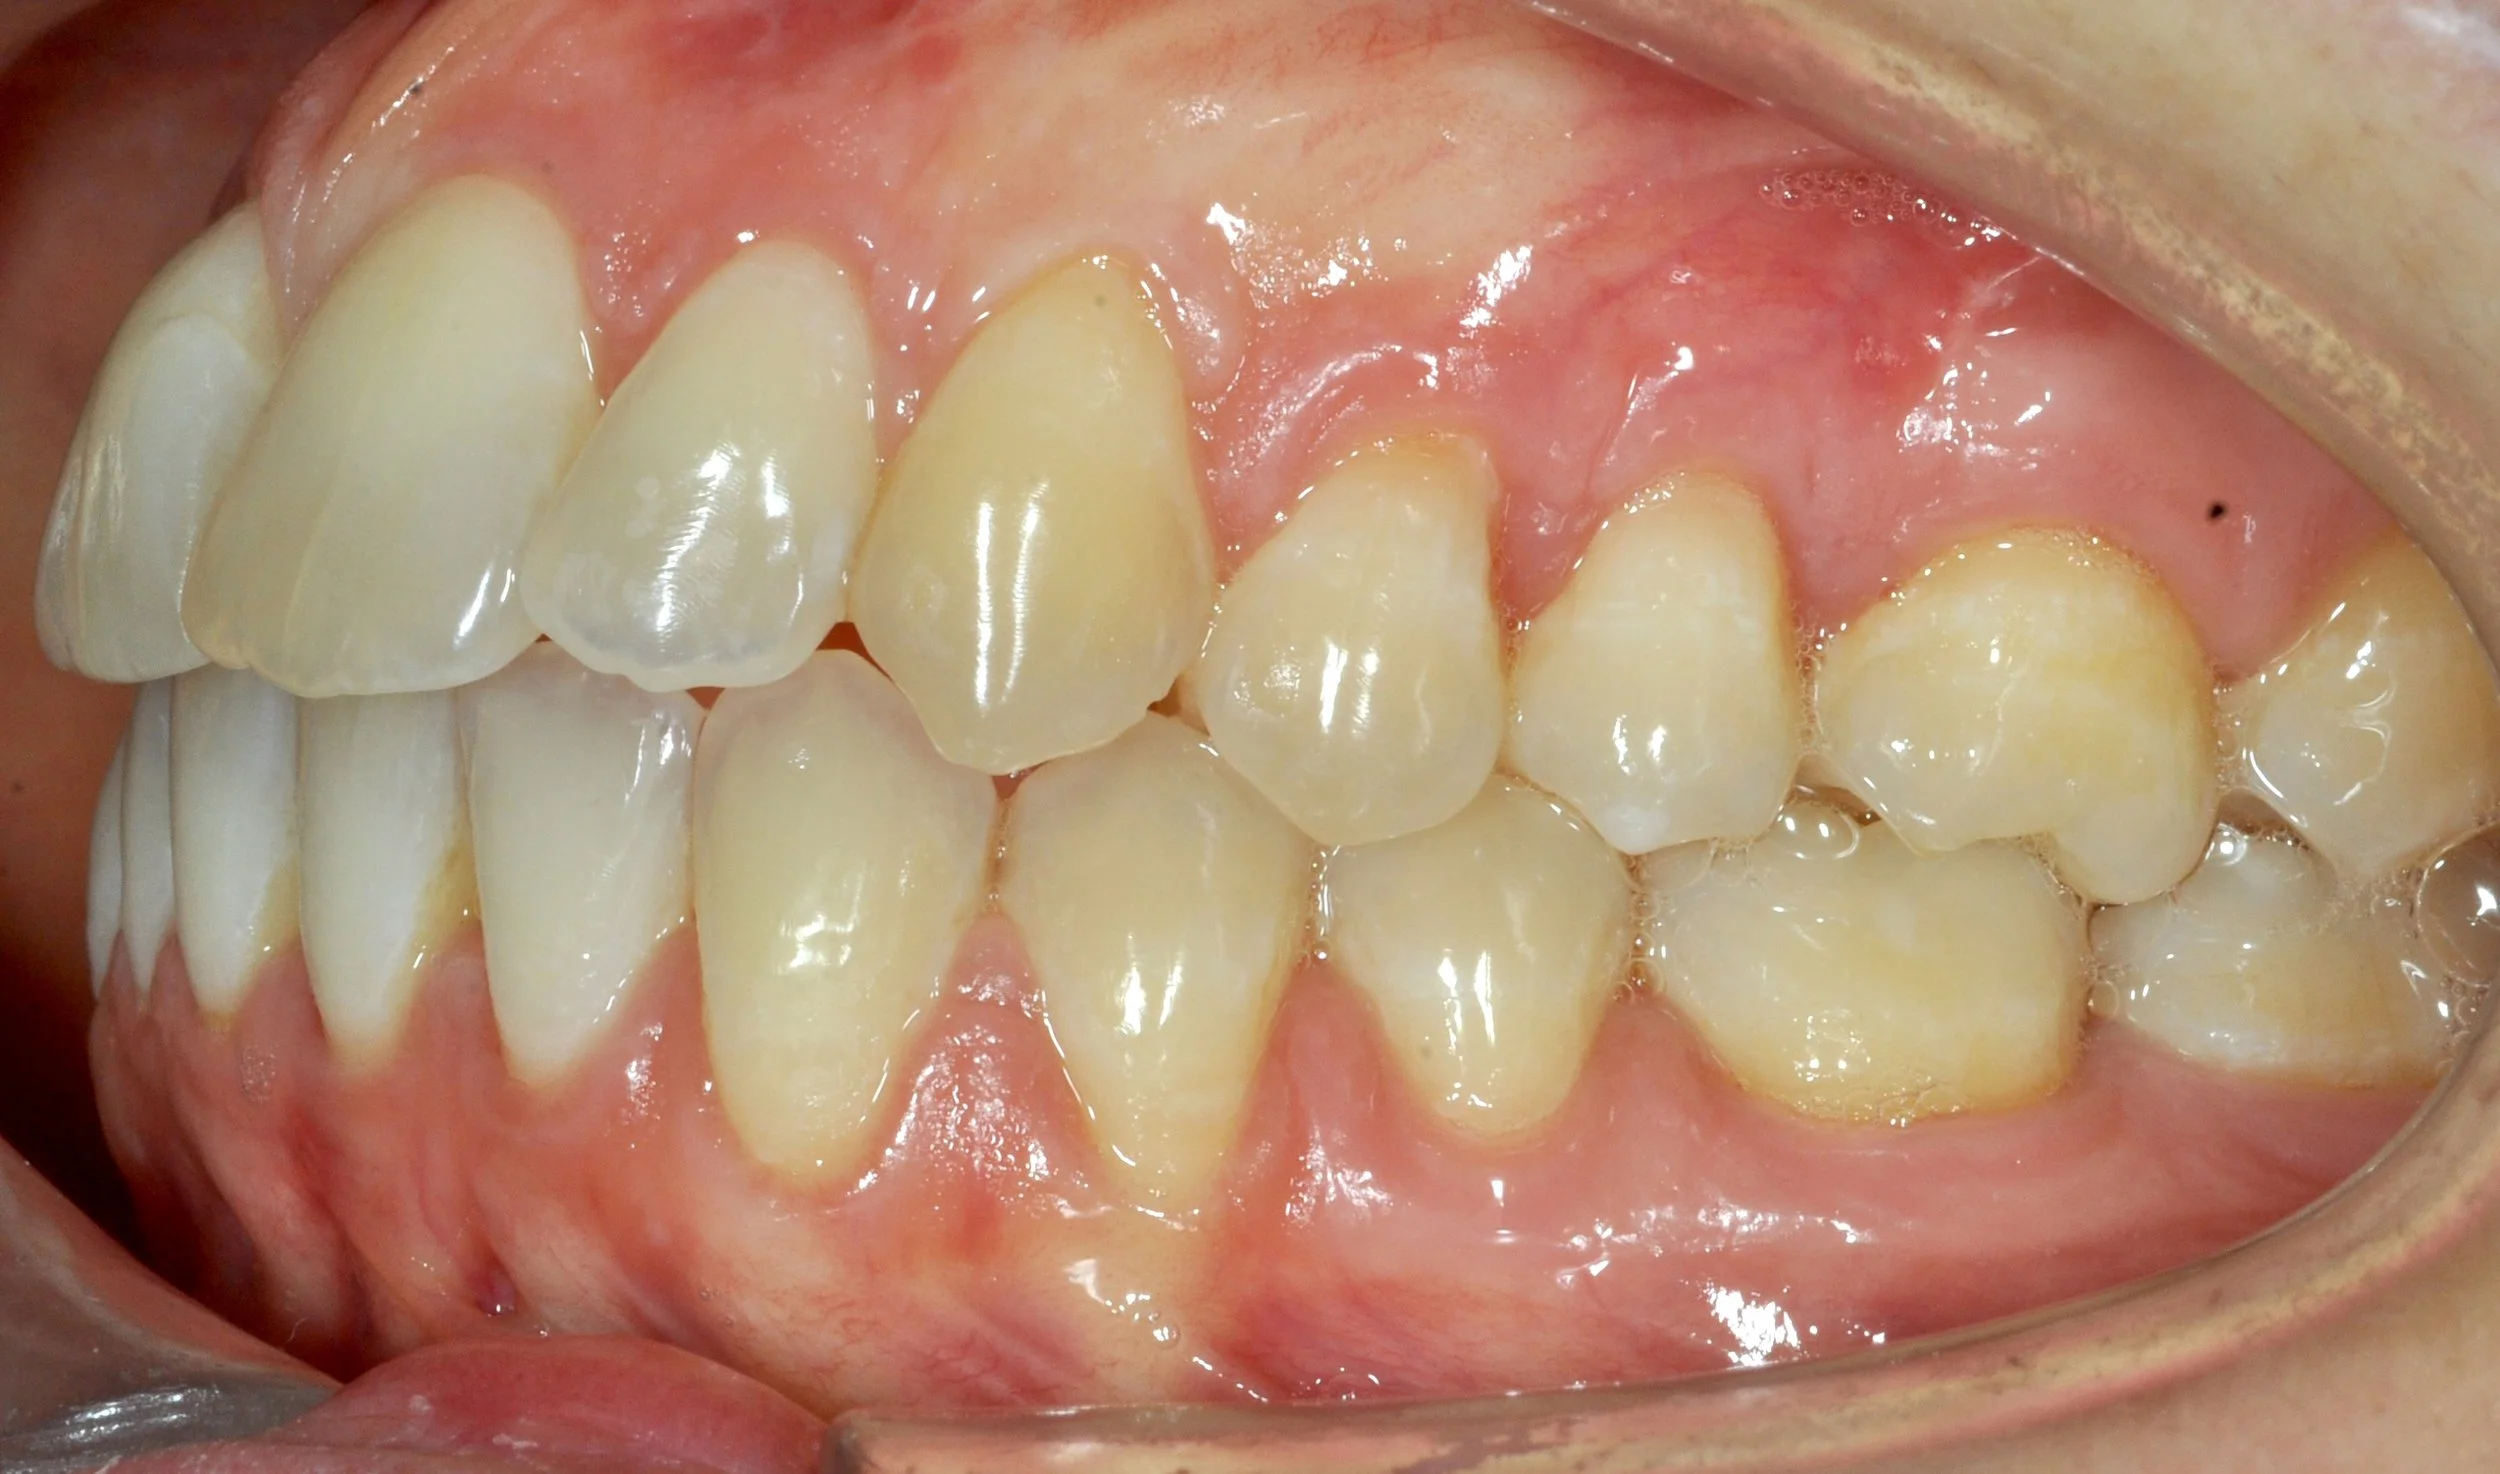

Giovane paziente in fase di crescita con denti superiori troppo in avanti rispetto agli inferiori, arcate strette e rotazioni importanti di alcuni elementi.

Grazie al trattamento con allineatori trasparenti, in 18 mesi è stato possibile accompagnare la crescita, correggere l’allineamento dei denti e migliorare il rapporto tra le arcate, ottenendo un sorriso più armonioso e funzionale.

PRIMA